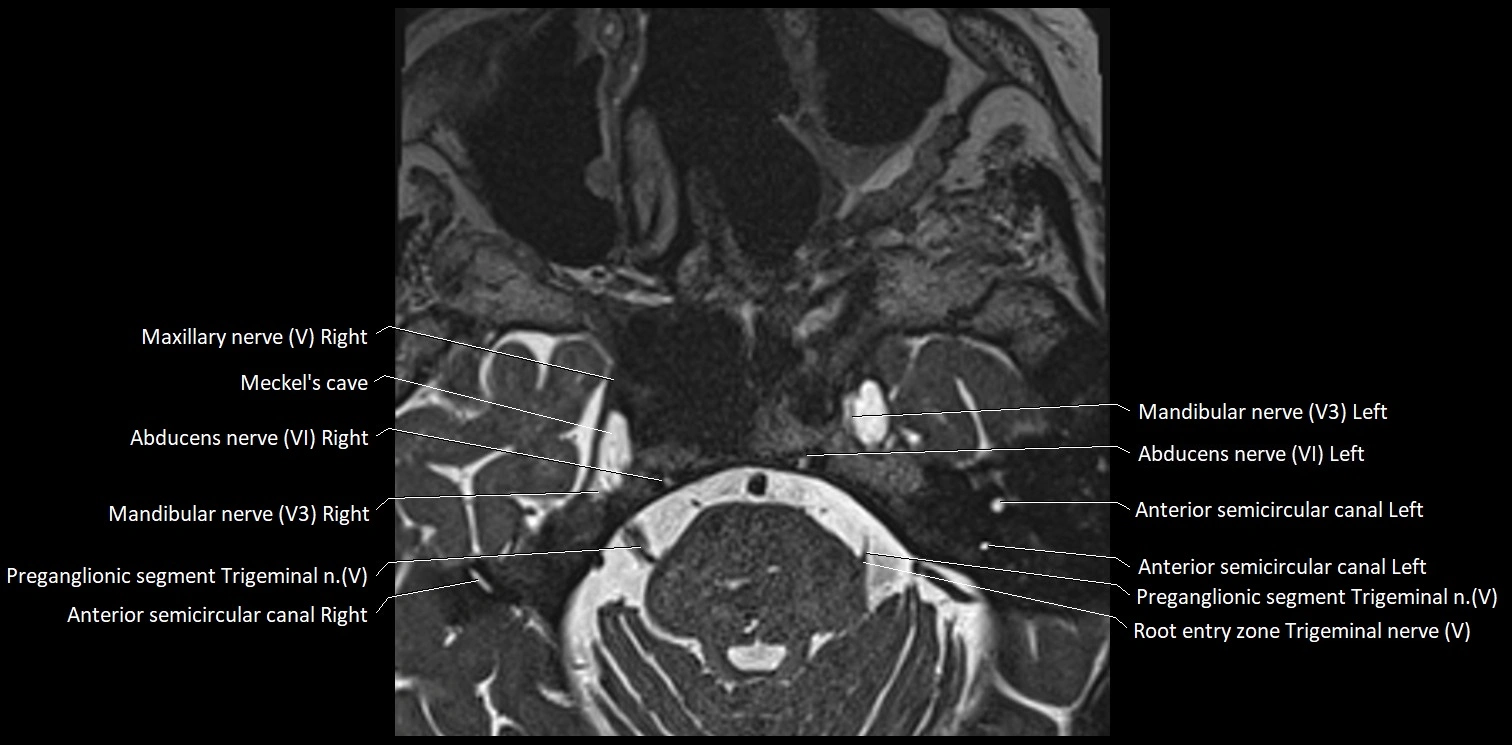

MRI Appearance

• The abducens nerve is a small, thin, linear structure

• Best visualized on high-resolution T2-weighted 3D MRI sequences (e.g., FIESTA or CISS)

• Seen as a hypointense (dark) line running from the brainstem at the pontomedullary junction, traversing the prepontine cistern, and entering Dorello’s canal under the petrosphenoidal ligament, then into the cavernous sinus, and finally the orbit

• May be challenging to visualize in standard MRI due to its small size

• Pathology may be inferred by absence, displacement, or enhancement of the nerve